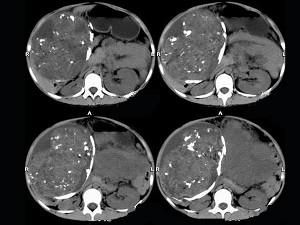

问题 女,43岁,发现盆腔包块3年,排尿困难6日,影像检查如图,最可能的诊断是()

选项 A.腹腔脂肪肉瘤 B.腹腔恶性间质瘤 C.腹腔畸胎瘤 D.腹腔畸胎瘤伴卵巢内胚窦瘤 E.卵巢内胚窦瘤

答案 D